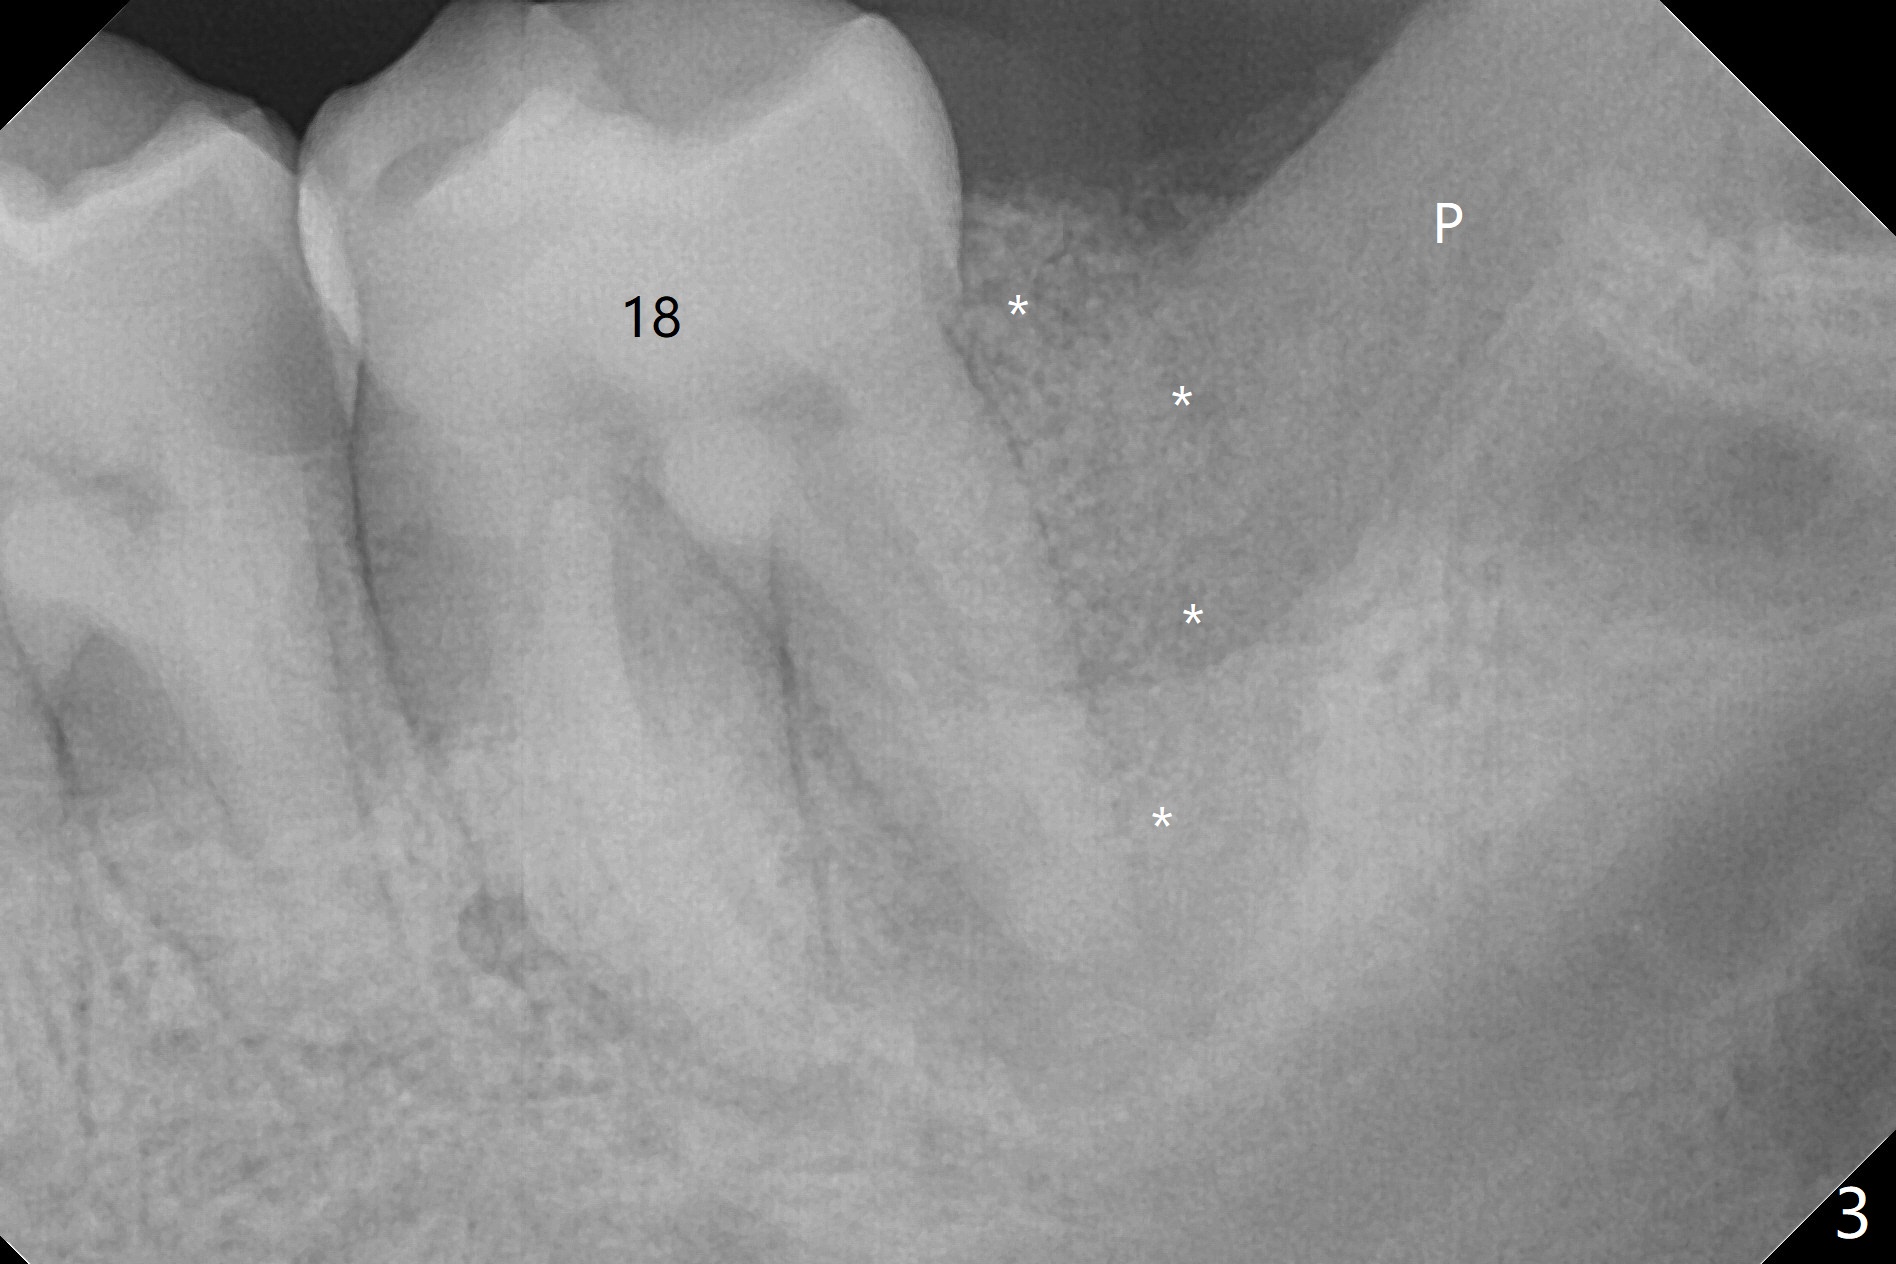

A 43-year-old man requests #17 extraction (Fig.1,2); the tooth #18 has large periapical radiolucency at the distal root. After SRP and extraction, Osteogen plug is placed in #17 sockets (Fig.3 P), while Vanilla Cancellous/Cortical Mix (allograft) 18 distal (*). The wound is closed with 4-0 plain gut suture. Similar to his son, he has crowding with #10 cross bite, #11 labioversion and a possible supernumerary tooth (11'). Seven months postop, not only does the periradicular radiolucency decrease around the distal root of the tooth #18 (Fig.4 *), but also the mesial and distal sockets of the 3rd molar heal (M, D). The patient is concerned about the sensitivity of the tooth #18, which is stable with the healthy gingiva. The sensitivity disappears 1 year postop, but there is a ~ 10 mm pocket distal of #18. Endo ice test shows necrosis. Endodontic referral is recommended. If endodontic treatment is not practical, periodontal referral is next step with laser modality.